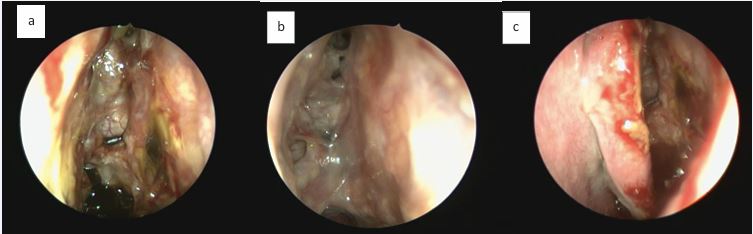

Reboot technique: step by step Reboot surgery is the technique that aims to completely remove the thickened and inflamed sinus mucosa, including all polyp formation in all affected sinuses, mainly involving the ethmoid and maxillary sinuses bilaterally, as well as part of the mucosa of the sphenoid and frontal sinuses. Furthermore, in case of edema or polyp formation on the middle turbinates, they must be adequately resected. The upper turbinates may also show polyp growth, which must be removed; however, the turbinates should be preserved as much as possible to maintain olfactory function. Additionally, the frontal sinuses may be involved, and a simple resection of the medial part of the frontal mucosa may be necessary, if sufficient space remains to maintain the opening long-term. Otherwise, a resection of the frontal sinus floor anteriorly and laterally may be indicated to maintain access. In cases of difficult access to the frontal sinus and/or extended frontal disease, it may be necessary to combine the Reboot technique with the DRAF III approach (full Reboot), to ensure access to the sinus and removal of the massively affected frontal mucosa.The surgeon must begin the procedure through a wide antrostomy and complete removal of the maxillary sinus mucosa, including the alveolar recess, using 30° and 70° endoscopes (Figures 1, 2 and 3).

Figure 1 Reboot surgery approach. Use of 360o rotating antrum forceps in the maxillary sinus, right side.

Figure 2 Reboot surgery approach. Image sequence showing the antrum grasping forceps (Heuwieser) removing polypoid mucosa from the entire right maxillary sinus.

Figure 3 Exposure of the periosteum of the right maxillary sinus after removal of the lining diseased mucosa.